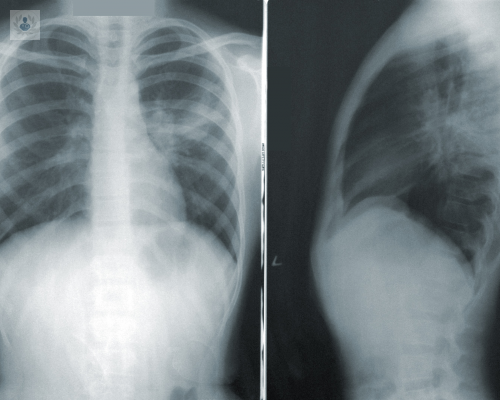

El abordaje del derrame pleural debe ser siempre de manera sistemática y ordenada; existen más de 50 causas posibles; tomando en cuenta la historia clínica y estudios de imagen. La integración de una ruta de las características del líquido pleural es una herramienta primordial para obtener un diagnóstico rápido y tratamiento óptimo.

El primer objetivo en el tratamiento para el derrame pleural es extraer el líquido (toracocentesis) de la cavidad para mejorar la fisiología respiratoria y la desaparición de los síntomas, seguido del diagnóstico a través de las pruebas mencionadas en la primera parte de este artículo.

Un derrame pleural puede ser provocado cuando existen procesos inflamatorios en el tórax, un ejemplo es la neumonía, en el que el 50% de los casos produce algo conocido como derrame paraneumónico.